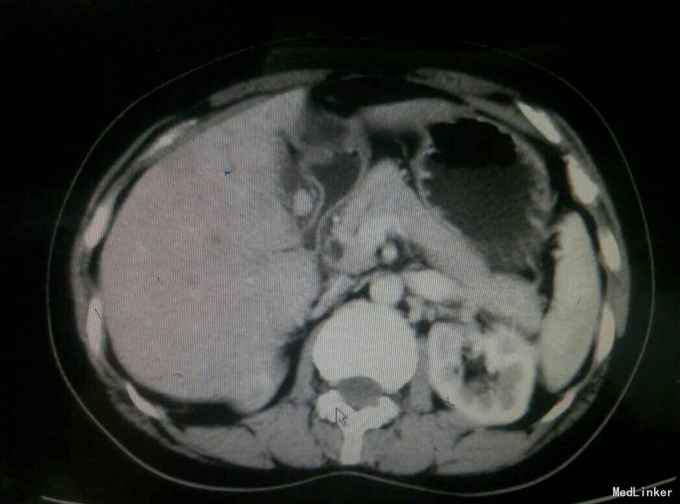

患者,女,43岁,左乳癌术后2年余,发现肝脏占位3天

查体:未及明显异常 辅助检查:腹部彩超发现肝脏多发占位,考虑转移,腹部增强CT:肝脏多发结节,考虑乳腺癌肝转移

诊断与治疗:乳腺癌术后伴肝转移,患者原病理为ER.PR阴性,Her-2高表达,术后行TE化疗、放疗以及靶向治疗,此次采取GX姑息性辅助化疗。

随访与讨论:患者入院时肝功能就偏高,也算是一个肝功能受损征相,而且彩超检查发现门静脉有癌栓形成,说明比较晚期,预后不良,所以采取姑息性辅助化疗,希望可以减轻患者病痛。当然同时也要排除其他地方转移,以采取相关治疗措施。